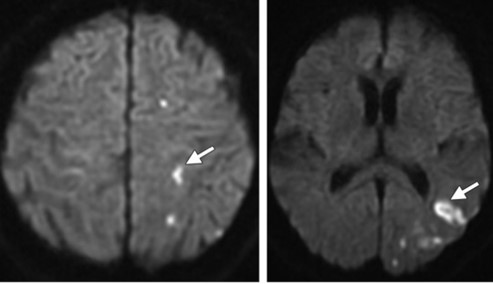

Los estudios de TC permiten evidenciar los accidentes cerebrovasculares (ACV) ocasionados por el abuso de la cocaína. Por caso, se localizó en la literatura imágenes que permiten ver el ACV isquémico agudo de la arteria cerebral media izquierda de un paciente. La TC sin contraste intravenoso visualiza la hipodensidad de la cabeza del caudado, del núcleo lenticular y de la ínsula izquierda. También se realizaron estudios de RM, que permiten observar la restricción del área isquémica en el territorio silviano(18) (ver Imagen 5).

Los consumidores habituales de cocaína suelen tener un pico de presión arterial sistólica elevada y un aumento de la frecuencia cardíaca tras el consumo, que los hace propensos a sufrir malformaciones arterovenosas. Al mismo tiempo, si esta sustancia se combina con etanol, las probabilidad de padecer una hemorragia subaracnoidea se incrementan. A propósito, se puede mencionar el caso de una paciente de 33 años de edad con síntomas de cefalea intensa y hemiparesia izquierda, en cuyo análisis de tóxicos de orina se detectó cocaína.(18)

En el caso que se viene reseñando, se realizó TC sin contraste para evidenciar eventuales daños isquémicos. En este estudio se localizó un hematoma intraparenquimatoso (ver Imagen 6). Este tipo de hematomas tiene un significativo riesgo para la persona, dado que puede avanzar hacia hemorragias con daño en la barrera hematoencefálica e incremento de la presión intracraneal, que puede ocasionar déficit neurológico e incluso la muerte.(17, 18)

En los casos de personas sin patología vascular subyacente, las hemorragias intraparenquimatosas se localizan con mayor frecuencia en los ganglios basales y el tálamo. Un caso como este se obtuvo en la literatura, correspondiente a una mujer de 23 años que sufrió una hemiplejía completa. Se le localizaron cantidades considerables de cocaína en el análisis de orina. La RM evidenció una isquemia en la rama MCA derecha con afectación de los ganglios basales(17) (ver Imagen 7).